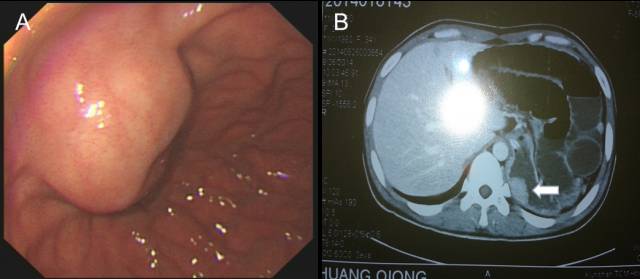

1.肝囊肿外压

胃底肝左叶区域可见粘膜下半球形隆起,表面光滑(图 A),EUS见类圆形无回声病灶外压,其后方回声增强,可见囊性病灶特有的双侧折射声影(图B白箭头),故诊断为肝左叶囊肿外压。

2.肝血管瘤

不同于低回声的囊肿,血管瘤的超声影像通常为中、高回声病灶,上面病例就是一个肝左叶类圆形血管瘤外压导致的胃底隆起。CT等传统影像工具诊断肝脏病灶不难,但部分与胃壁关系密切的外生性血管瘤却是例外。